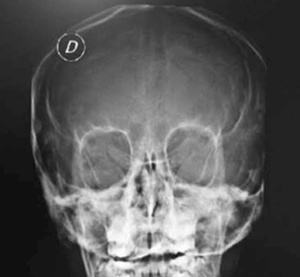

Adolescente de 13 años, sexo femenino, procedente de Montevideo, buen crecimiento y desarrollo, carné esquema de vacunación vigente, medio social, económico y cultural aceptable. Antecedentes familiares de padre y hermana con asma, abuela paterna con asma y aspergilosis broncopulmonar alérgica a los 50 años. La primera evaluación por neumología fue a los 9 años, se presenta con tos crónica catarral desde los 6 meses de vida, sin predominio estacional, no expectoración, drenaje postural, broncorrea, ni sinusitis. Se acompañaba de otitis crónica serosa que requirió colocación de tubos transtimpánicos a los 4 años, con persistencia de secreciones de oído medio, hipoacusia e impedanciometrías alteradas. Al examen se destaca: índice de masa corporal (IMC): 16,7 kg/m² (percentil 15); pleuropulmonar: frecuencia respiratoria 16, saturación de oxígeno ventilando espontáneamente al aire 98%, pico flujo espirado 350 L/m, moviliza secreciones con la tos, no remodelación de tórax, ni hipocratismo digital. No presentaba pólipos en la rinoscopía. Cardiovascular normal. En la radiografía de tórax se observa opacidad inhomogénea en lóbulo medio (Figura 1). La radiografía de senos faciales muestra opacidad de ambos senos maxilares (Figura 2). Con sospecha de bronquiectasias se solicitan estudios para descartar FQ, inmunodeficiencias, malformación congénita de la vía aérea y discinesia ciliar. Los resultados de tres test del sudor fueron normales: Cl 23 meEq/l (159 mg sudor), Cl 14 mEq/l (215 mg), Cl 19 mEq/l (180 mg), y la evaluación inmunológica fue normal. El exudado faríngeo no desarrolló gérmenes. La tomografía de tórax de alta resolución muestra múltiples bronquiectasias en lóbulo medio, disminuido de tamaño por atelectasia (Figura 3). Se realiza fibrobroncoscopía con lavado bronquioalveolar, en vistas de valorar la vía aérea, y valoración infecciosa. Se descarta lesión anatómica o dinámica en la vía aérea y cuerpo extraño, y el estudio bacteriológico y micológico fueron negativos. Con sospecha de DCP, se realiza biopsia de la mucosa bronquial y microscopía electrónica. Las muestras obtenidas fueron fijadas en glutaraldehído al 2,5% en tampón fosfato 0,1 M (pH: 7,2 - 7,4), y trasladadas a 4 grados al laboratorio de biología celular, Instituto de Investigaciones Biológicas Clemente Estable. Se observaron alteraciones ultraestructurales consistentes con DCP. Se realiza cepillado nasal de ambas fosas nasales, observadas vivas e incubadas a 37° al microscopio de contraste de fase en medio de cultivo médium 199 para determinar morfología, frecuencia y patrón de batido ciliar, constatándose movilidad ausente en todos los campos. La microscopía electrónica muestra ultraestructura ciliar con patrón 9+2, con ausencia de ambos brazos de dineína. El diagnóstico de funcionalidad con inmovilidad ciliar absoluta, cilios de ultraestructura con defecto de brazos internos y externos de dineína, confirma la DCP. Se solicita estudio genético molecular con secuenciación del gen DNAH5, que muestra una variante probablemente patológica con presencia en homocigosis de una duplicación c.10196dupT mutación frameshift p. Cys3400Metfsx54, no se encuentra en base de datos ni en la bibliografía consultada, y otra de significado incierto con presencia en heterocigosis de la variante c.A8387G: p.D2796G en el gen DNAH5. En la evolución, la paciente persiste con igual sintomatología, los cultivos de expectoración iniciales fueron negativos. A los 13 años el estudio bacteriológico de expectoración desarrolla Pseudomonas aeruginosa, se realiza tratamiento con gentamicina nebulizada y ciprofloxacina vía oral por 21 días. Los cultivos de control muestran desarrollo de Pseudomonas aeruginosa, por lo que se indica tobramicina inhalada por 28 días. Persiste desarrollo de abundantes colonias y se inicia colistina nebulizada cada 12 horas, inicialmente por tres meses, luego mensual alternando con tobramicina inhalada. De la evolución funcional, presentó espirometrías normales, con valores de volumen espiratorio forzado en el primer segundo (VEF1) estables de 95% del predicho, distancia recorrida en 6 minutos sin desaturación en la mar cha, ecocardiograma Doppler normal y audio metrías normales. En la tomografía de tórax, a los 13 años, persisten bronquiectasias asociadas a atelectasia en lóbulo medio, sin cambios significativos con respecto a la tomografía previa, hiperinsuflación compensadora del resto de los lóbulos; aisladas bronquiectasias en segmento basal medial de lóbulo inferior derecho, aso ciado a imágenes de árbol en brote. Agrega bronco rrea mucopurulenta 10 cc al día. Presentó adecuada adhe rencia al tratamiento con fisioterapia dos veces por día en domicilio, asistida por fisioterapeuta tres veces a la semana. El tratamiento antibiótico continuó con colistina nebulizada y cipro floxacina vía oral. Realiza ejer cicio y danza de forma regular.